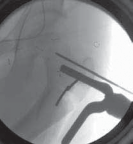

--- TECH FIG 2 • Intraoperative C-arm–guided insertion of the seating chisel for the blade plate.A. Insertion of the guide pin in the superior part of the neck at right angles to the long axis of the femur. B. Position of the guide pin along the midfemoral neck axis in the frog-leg lateral view. C. Position of the seating chisel parallel to the guide pin and perpendicular to the long axis of the femur. D. Position of the seating chisel parallel to the guide pin and along the midfemoral neck axis on the frog-leg lateral view. E. The seating chisel is backed out from its final position to disimpact the chisel before the osteotomy.Pr FiAE

TECHNIQUES A B CTECH FIG 3 • Completion of transverse osteotomy, derotation, and fixation with 90-degree blade plate.A. Level of the osteotomy is at upper end of the lesser trochanter 1.5 cm below the seating chisel. Two parallel AP guide pins proximal and distal to the osteotomy line are used to judge the magnitude of derotation. B,C. Transverse osteotomy parallel to the seating chisel and perpendicular to the long axis of the femur. lated, which necessitates removal of the guide pin (in addition to the seating chisel) at the time of insertion of the blade plate, which removes an important guide for its introduction.

3. The level of the transverse osteotomy is marked on the bone with a marking pen or cautery. This is done about

1 to 1.5 cm below the level of the seating chisel, at the upper end or just proximal to the lesser trochanter (

TECH FIG 3A

).

4. The periosteum is elevated circumferentially at this level to allow placement of protective retractors during the osteotomy.

5. Two smooth pins (2.5-mm Kirschner wires) are placed in an anterior-to-posterior direction parallel to each other and perpendicular to the long axis, just proximal and distal to the proposed osteotomy site respectively (